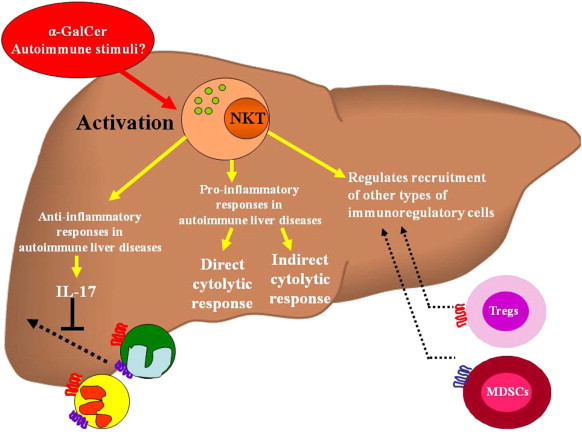

Autoimmune Liver Diseases

Autoimmune liver diseases are conditions in which the body's immune system mistakenly attacks healthy liver cells, leading to inflammation and damage. Two common autoimmune liver diseases are autoimmune hepatitis (AIH) and primary biliary cholangitis (PBC).